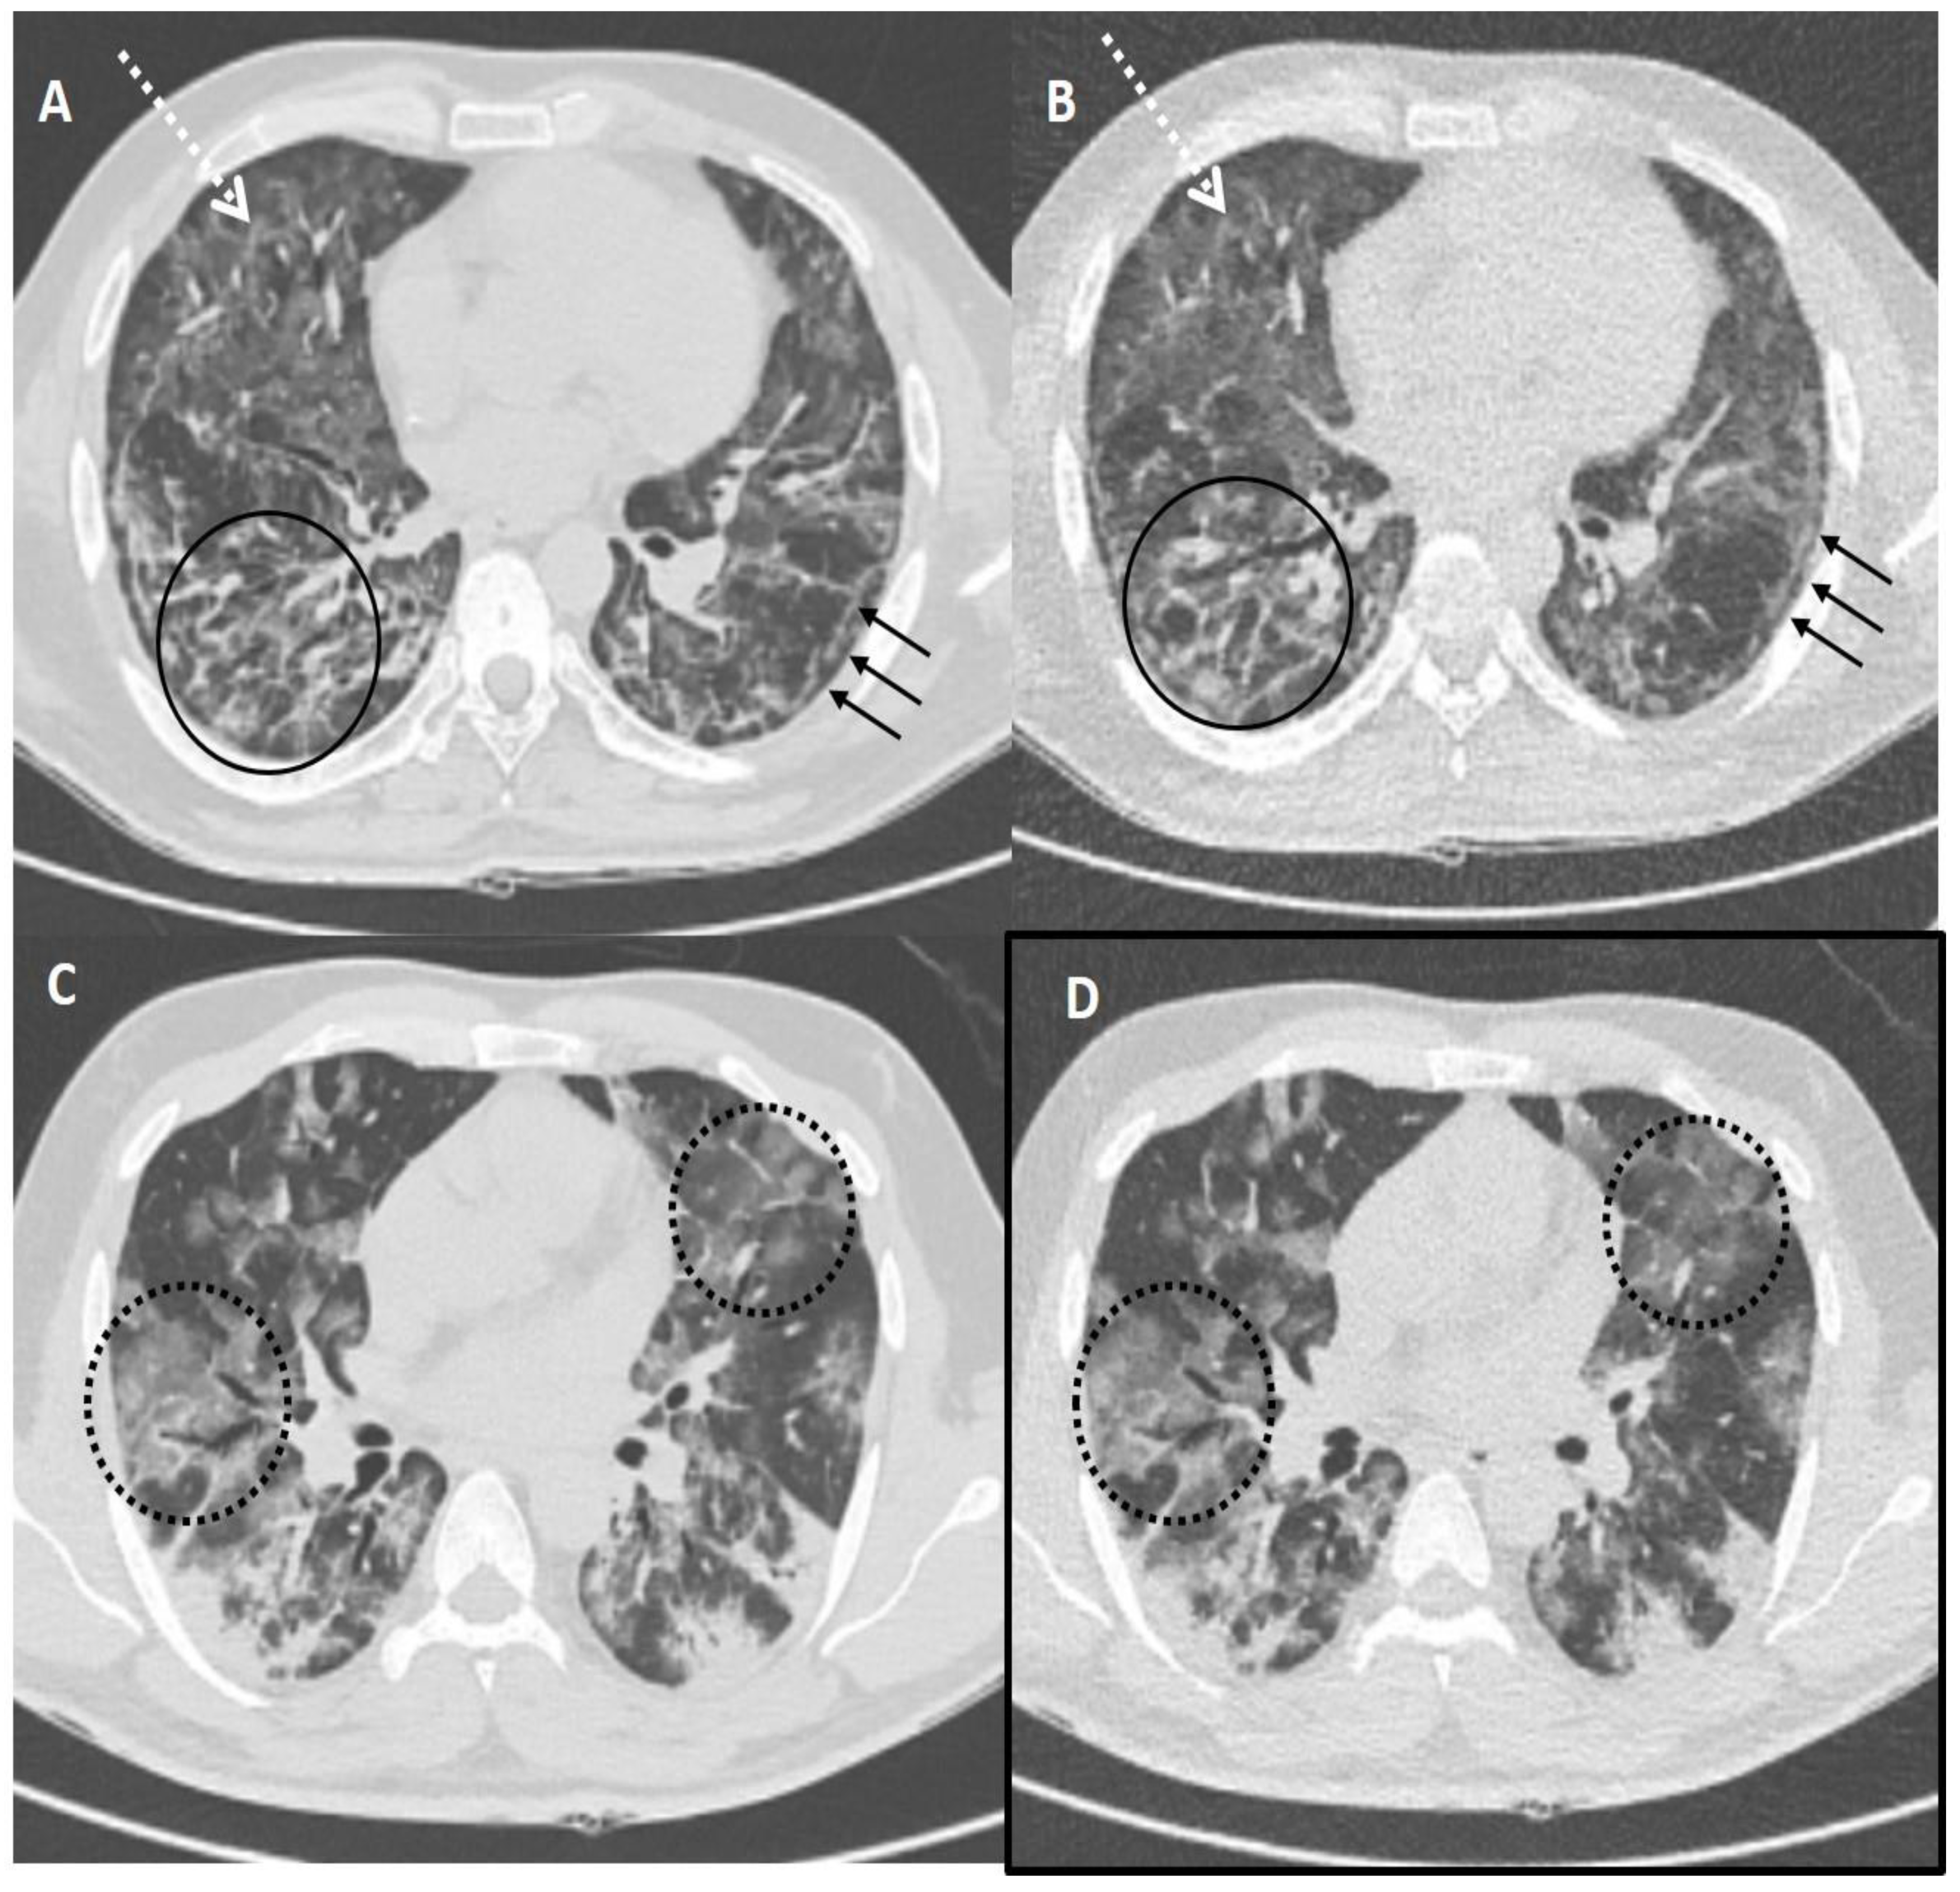

Figure 4.

Comparison of standard-dose CT (SDCT) chest and ultra-low dose CT (ULDCT) chest in two different COVID-19 patients: (A,B) A 51-years old male with SDCT (A) and corresponding ULDCT (B) images showing interlobular septal thickening/reticulation (black circles) and parenchymal bands (black arrows), with interspersed areas of GGOs in both lungs (dotted white arrows). (C,D) A 45-years old male patient with SDCT chest (C) and corresponding ULDCT chest (D) showing areas of GGOs with interlobular septal thickening giving a crazy-paving pattern (dotted circles). The CT severity score calculated on SDCT and ULDCT was found to be similar in both patients, while the effective radiation dose for SDCT was 4.63 mSv and 4.81 mSv, and for ULDCT was 0.26 mSv and 0.28 mSv, respectively.